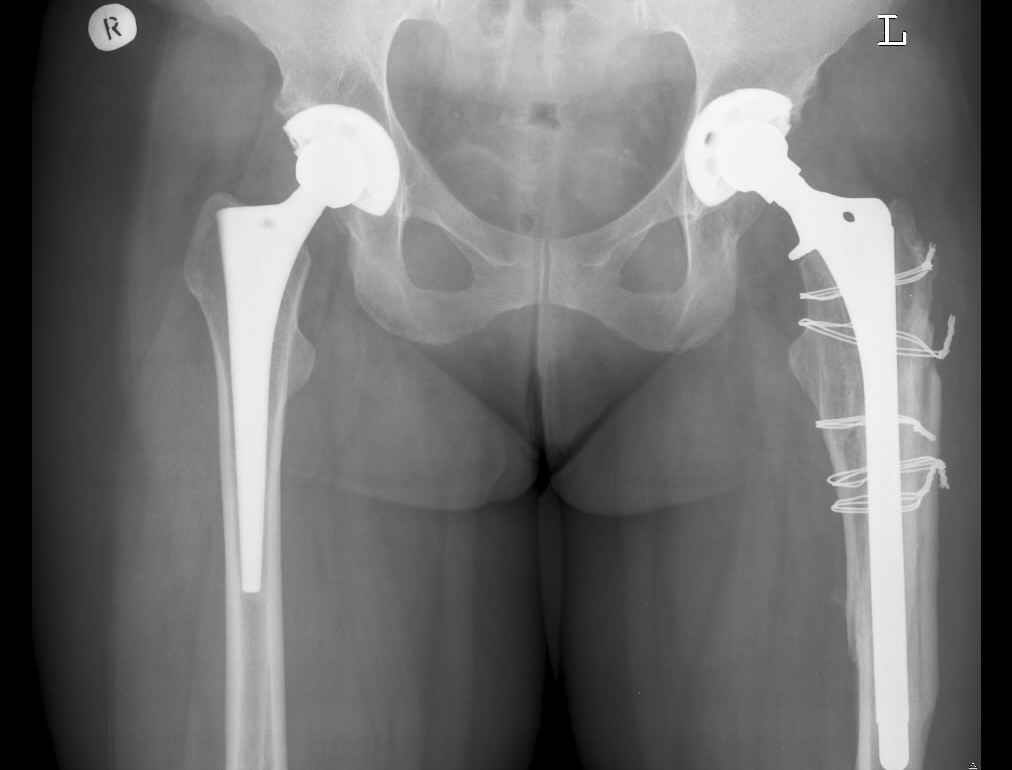

Анамнез: Болеет с 1995 года. В 2000 и 2001 годах произведено тотальное эндопротезирование обоих тазобедренных суставов (сначала левого затем правого). Сейчас в области левого бедра в в/3 имеется резкий отек, боль, крепитация. Диагноз:Состояние после тотального эндопротезирования обеих Т\Б суставов, перелом в/3 левого бедра. Нога уложена на шину Беллера с дисциплинирующим вытяжением. Тактика оперативного лечения? Заранее благодарю! С уважением, А.В.Владзимирский Донецкий НИИ травматологии и ортопедии

В очередной раз вызывает удивление установка биполяра у молодого пациента, но дело не в этом. Имеется перелом с нестабильностью бедренного цементного компонента. Значительный дефект костной ткани проксимального отдела бедра.

Следует убрать ножку и остатки цемента, заменить на Вагнеровскую ножку (в крайнем случае на длинную цементную), добавить костную пластику проксимального отдела. Тазовый компонент заодно заменить на бесцементный.

Уважаемый Антон,

По Ванкуверовской классификации это 2А тип перипротезного перелома на фоне нестабильности ножки эндопротеза и остеолиза проксимального отдела бедра. Решение - удаление предыдущей ножки, имплантация ножки дистальной фиксации. Канал виден на ограниченном участке, исходя из увиденного, я бы предпочел цилиндрическую ножку 200 мм полнопокрытую. Фрагменты собрал бы вокруг ножки серкляжами. Если будут мелкие фрагменты, то есть смысл взять кортикальные аллографты и поджать фрагменты по типу вязанки хвороста. Отношение к чипсам двоякое - на любителя, главное - надежная дистальная фиксация ножки, обеспечивающая первичную стабильность. Что-то похожее мы оперировали несколько лет назад, качество первичных Р-грамм оставляет желать лучшего, но суть понятна. Результаты через 3 года.

Уважаемый коллега! Абсолютно согласна с мнением Рашида Муртузалиевича Тихилова: это перелом на фоне нестабильности, необходима длинная ножка с дистальной фиксацией, и без серкляжа не обойтись. Впадину тоже придется заменить.